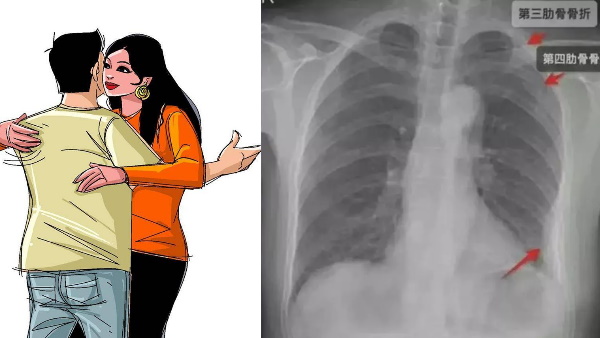

एक्स-रे में निकली तीन टूटी हड्डियां

धीरे-धीरे महिला के सीने में दर्द बढ़ने लगा तो महिला ने 5 दिन बाद डॉक्टर के पास जाने का सोचा। डॉक्टर ने जब उसका एक्स-रे किया तो पता चला की महिला की तीन पसलियां टूट गई हैं। दो पसलियां दाएं रिब केज में एक पसली बाएं रिब केज में टूटी है। जिसके बाद उस महिला का काफी दिनों तक इलाज चला जिसके लिए उसे ऑफिस से छुट्टी भी लेनी पड़ी।